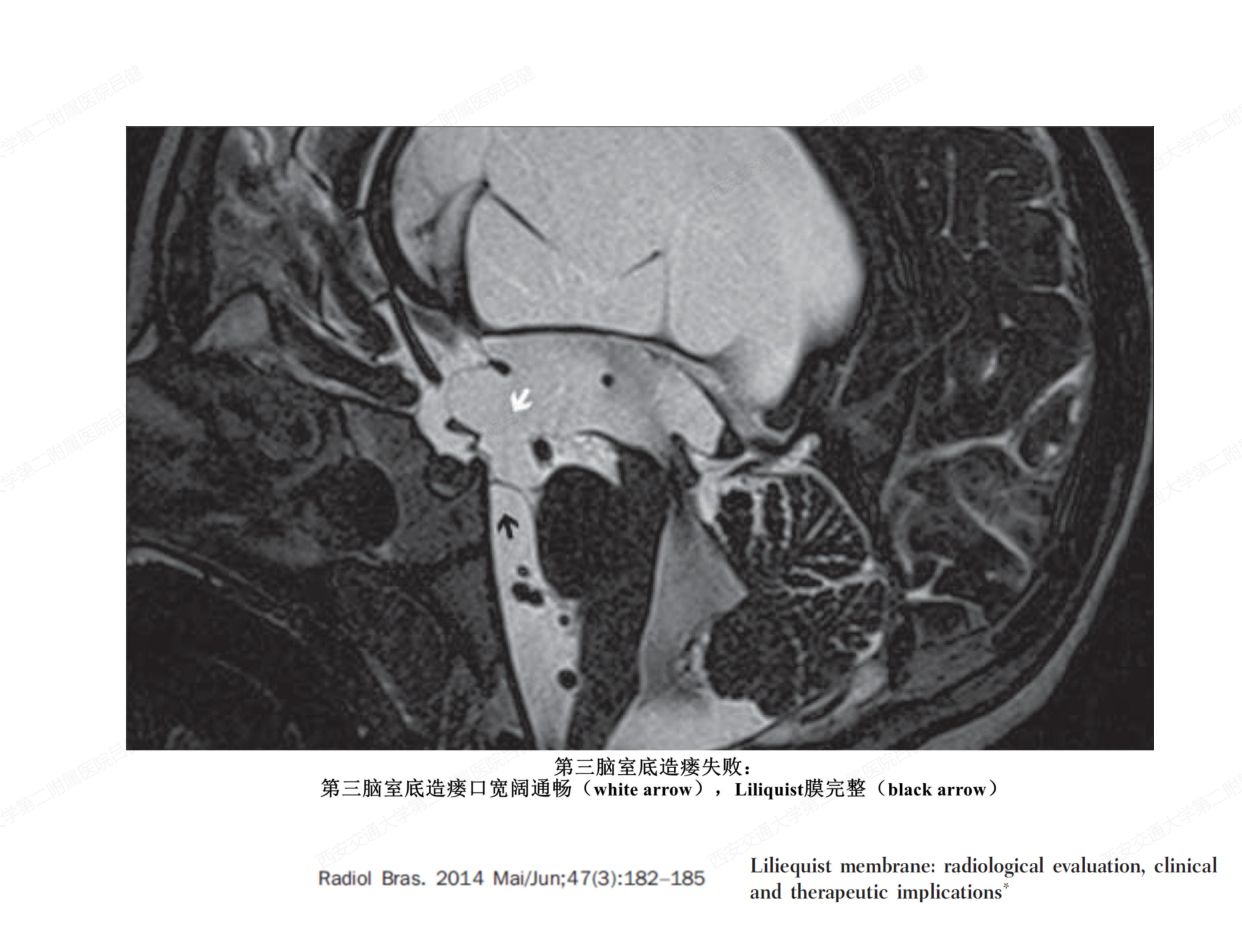

颅内蛛网膜和蛛网膜下池的解剖学研究意义

转自 神外前沿2020-6-22 解剖课件| 颅内蛛网膜和脑池的解剖研究-西交二院吕健